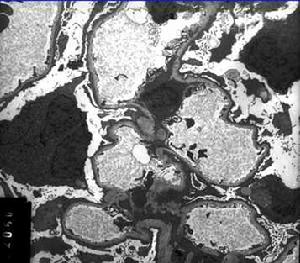

(3)Lange等用螢光抗體法曾發現在腎小球系膜細胞中及腎小球基底膜上有鏈球菌抗原,在電鏡下觀察到腎小球基底膜與上皮細胞足突之間有緻密的塊狀駝峰樣物存在,內含免疫複合物及補體。患者腎小球上IgG及C3呈顆粒狀沉著。患者腎小球中有補體沉著、多形核白細胞及單核細胞浸潤,表明這三類炎症介導物質進一步促進了病變的發展巨噬細胞增殖在病變發展中也起重要作用。NF-κB核轉錄因子在免疫系統的細胞中起關鍵性作用,NF-κB調節涉及腎小球腎炎發病機制中許多致炎性細胞因子和細胞黏附分子基因轉錄。

妊娠合併急性腎小球腎炎大部分患者恢復較快,上述變化在短期內可完全消失,少數患者腎小球毛細血管蒂部間質細胞增殖及沉積物消失需歷時數月或更長,少數患者病變繼續發展,腎小球囊上皮細胞增殖較為明顯並可與腎小球毛細血管叢粘連局部形成新月體,巨噬細胞增殖也可形成新月體,逐漸轉入慢性。在嚴重的病例,進球小動脈及腎小球毛細血管可發生纖維素樣壞死及血栓形成,或上皮細胞和巨噬細胞顯著增殖,可轉變為新月體性腎炎,短期導致腎功能衰竭。